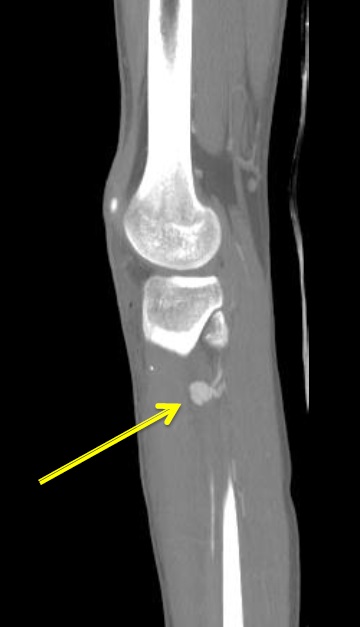

腹部脏器和腹膜后实性脏器损伤出血治疗的趋势是非手术治疗(nonoperative management,NOM),其成功率在脾损伤>50%,肝损伤>60%,肾损伤几乎100%。 实性脏器损伤包括减速伤和直接损伤,大多数实质性脏器损伤都累及相关动脉中小分支导致脏器实质内出血。血管内治疗的适应症包括血流动力学稳定或通过输液稳定的病人以及外科手术禁忌症的病人,影像学特征包括活动性出血,动-静脉瘘,以及假性动脉瘤形成(Lopera JE Semin Intervent Radiol 2010)。脏器损伤的血管治疗技术包括选择性导管技术进行靶血管微粒或明胶海绵栓塞或近端微弹簧栓子的栓塞,以及超选择导管技术微弹簧栓子Trapping栓塞(sandwich,前后门技术),覆膜血管支撑架技术仅用于在技术可行情况下的实质脏器外动脉的出血治疗。主要并发症包括实质脏器的梗死/坏死,脓肿形成,相关组织器官的缺血等。 弹簧栓子栓塞的要点包括

包括局部血管喷射、造影剂外溢、血管中断、假性动脉瘤和血管夹层